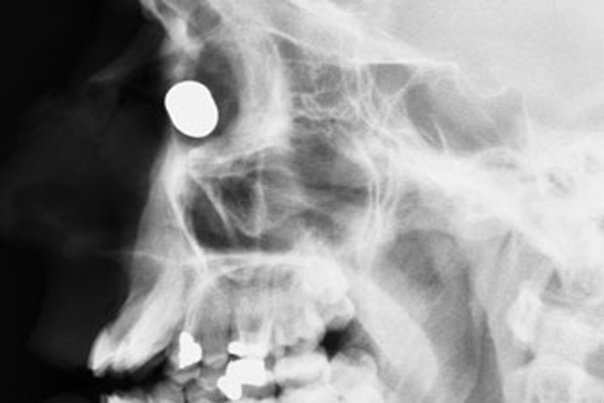

2. Snimka pokazuje čavao u glavi Georgea Chandlera iz savezne države Kansas. Chandler i prijatelj radili su na projektu kada je pištolj za ispaljivanjE čavala iznenada opalio. Chandler je kasnije izjavio kako nije znao gdje je metak završio ali je osjetio lagani ubod na vrhu glave.

4. Daniel Greenwood iz Manchestera preživio je hitac s male udaljenosti nakon borbe s pljačkašem koji je u njega uperio pištolj.